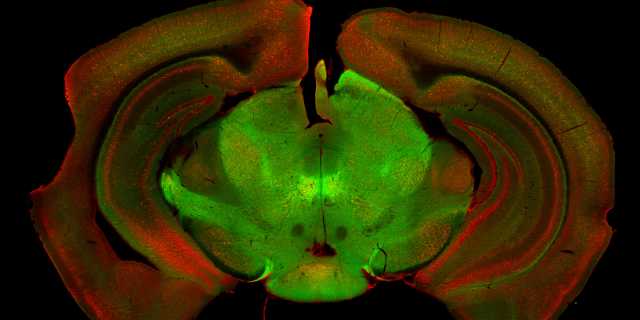

Das Forschungsteam hat dazu die Substantia nigra anatomisch, genetisch und funktionell untersucht. Es zeigte sich, dass diese Region aus mehreren unterschiedlichen Typen von Nervenzellen besteht. Für zwei der Populationen haben die Forscher nun die genaue Funktion aufgeklärt: Während die eine Population für die Ingangsetzung einer gewünschten Bewegung verantwortlich ist, sorgt die zweite für deren Fortführung.

Zwei neuronale Zellpopulationen (grün, rot) in der Substantia nigra, die für die Steuerung der Bewegung verantwortlich sind.